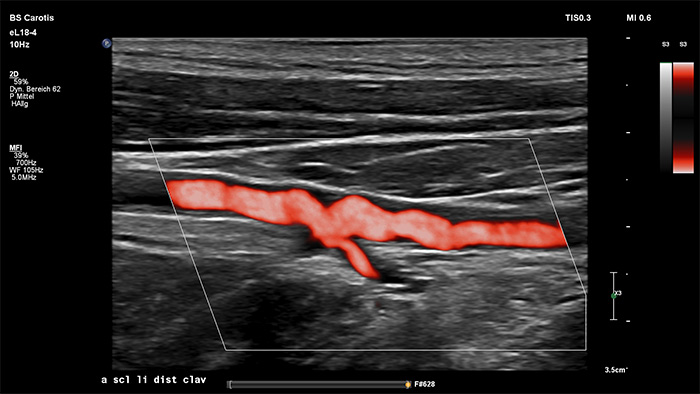

Philips MicroFlow Imaging wurde für die Erkennung langsamer und schwacher Blutflüsse in Gewebe entwickelt und verbessert bei Gefässuntersuchungen die Flussauflösung mit beeindruckender Empfindlichkeit. Subtile, pathologische Strömungsverhältnisse um stenotische Plaques lassen sich durch die hohe Auflösung und minimale Artefakte visualisieren und charakterisieren, was die Diagnosesicherheit unterstützt.